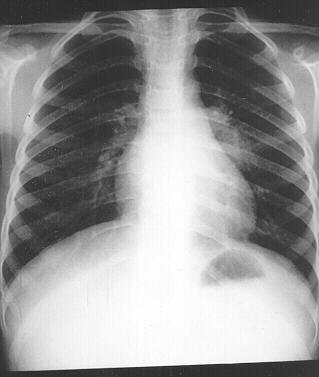

TB disease usually occurs in the lungs (pulmonary TB), but it can also occur in other places in the body (extrapulmonary TB). Miliary TB occurs when

tubercle bacilli enter the bloodstream and are carried to all parts of the body, where they grow and cause disease in multiple sites.